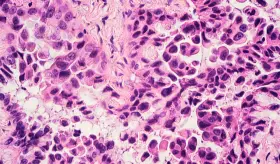

Radiólogo especialista destaca la importancia de la visión independiente del profesional en imágenes diagnósticas para detectar fibrosis pulmonar progresiva y guiar tratamientos específicos según cada patología autoinmune.

El análisis de 871 tumores pulmonares en no fumadores reveló que vivir en zonas contaminadas se asocia a mutaciones relacionadas con el envejecimiento y el tabaquismo, así como a telómeros más cortos, un signo de envejecimiento celular acelerado.

Aunque las tasas de tabaquismo han disminuido significativamente en las últimas décadas, el cáncer de pulmón vuelve a posicionarse como una de las principales causas de muerte por cáncer en el mundo.